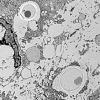

5 Myositis & EM